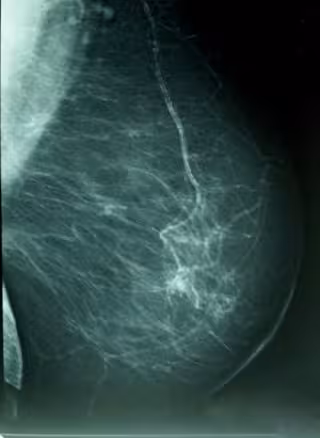

WIKIPEDIA/A. AVENDAÑO